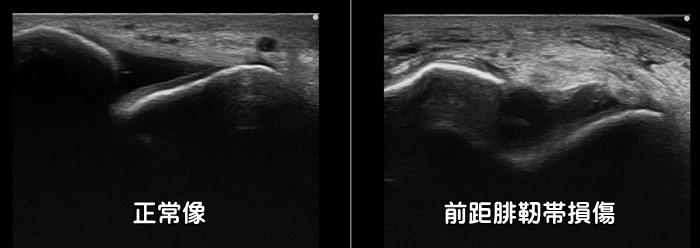

足首の捻挫・前距腓靭帯損傷

足首の捻挫で最も損傷を受ける靭帯が前距腓靭帯です。エコー検査では靭帯の断裂の有無を確認できます。特に子供では剥離骨折を合併するリスクが高い為に要注意です。初期の適切な治療が重要です。炎症反応の動画はこちらで確認できます。